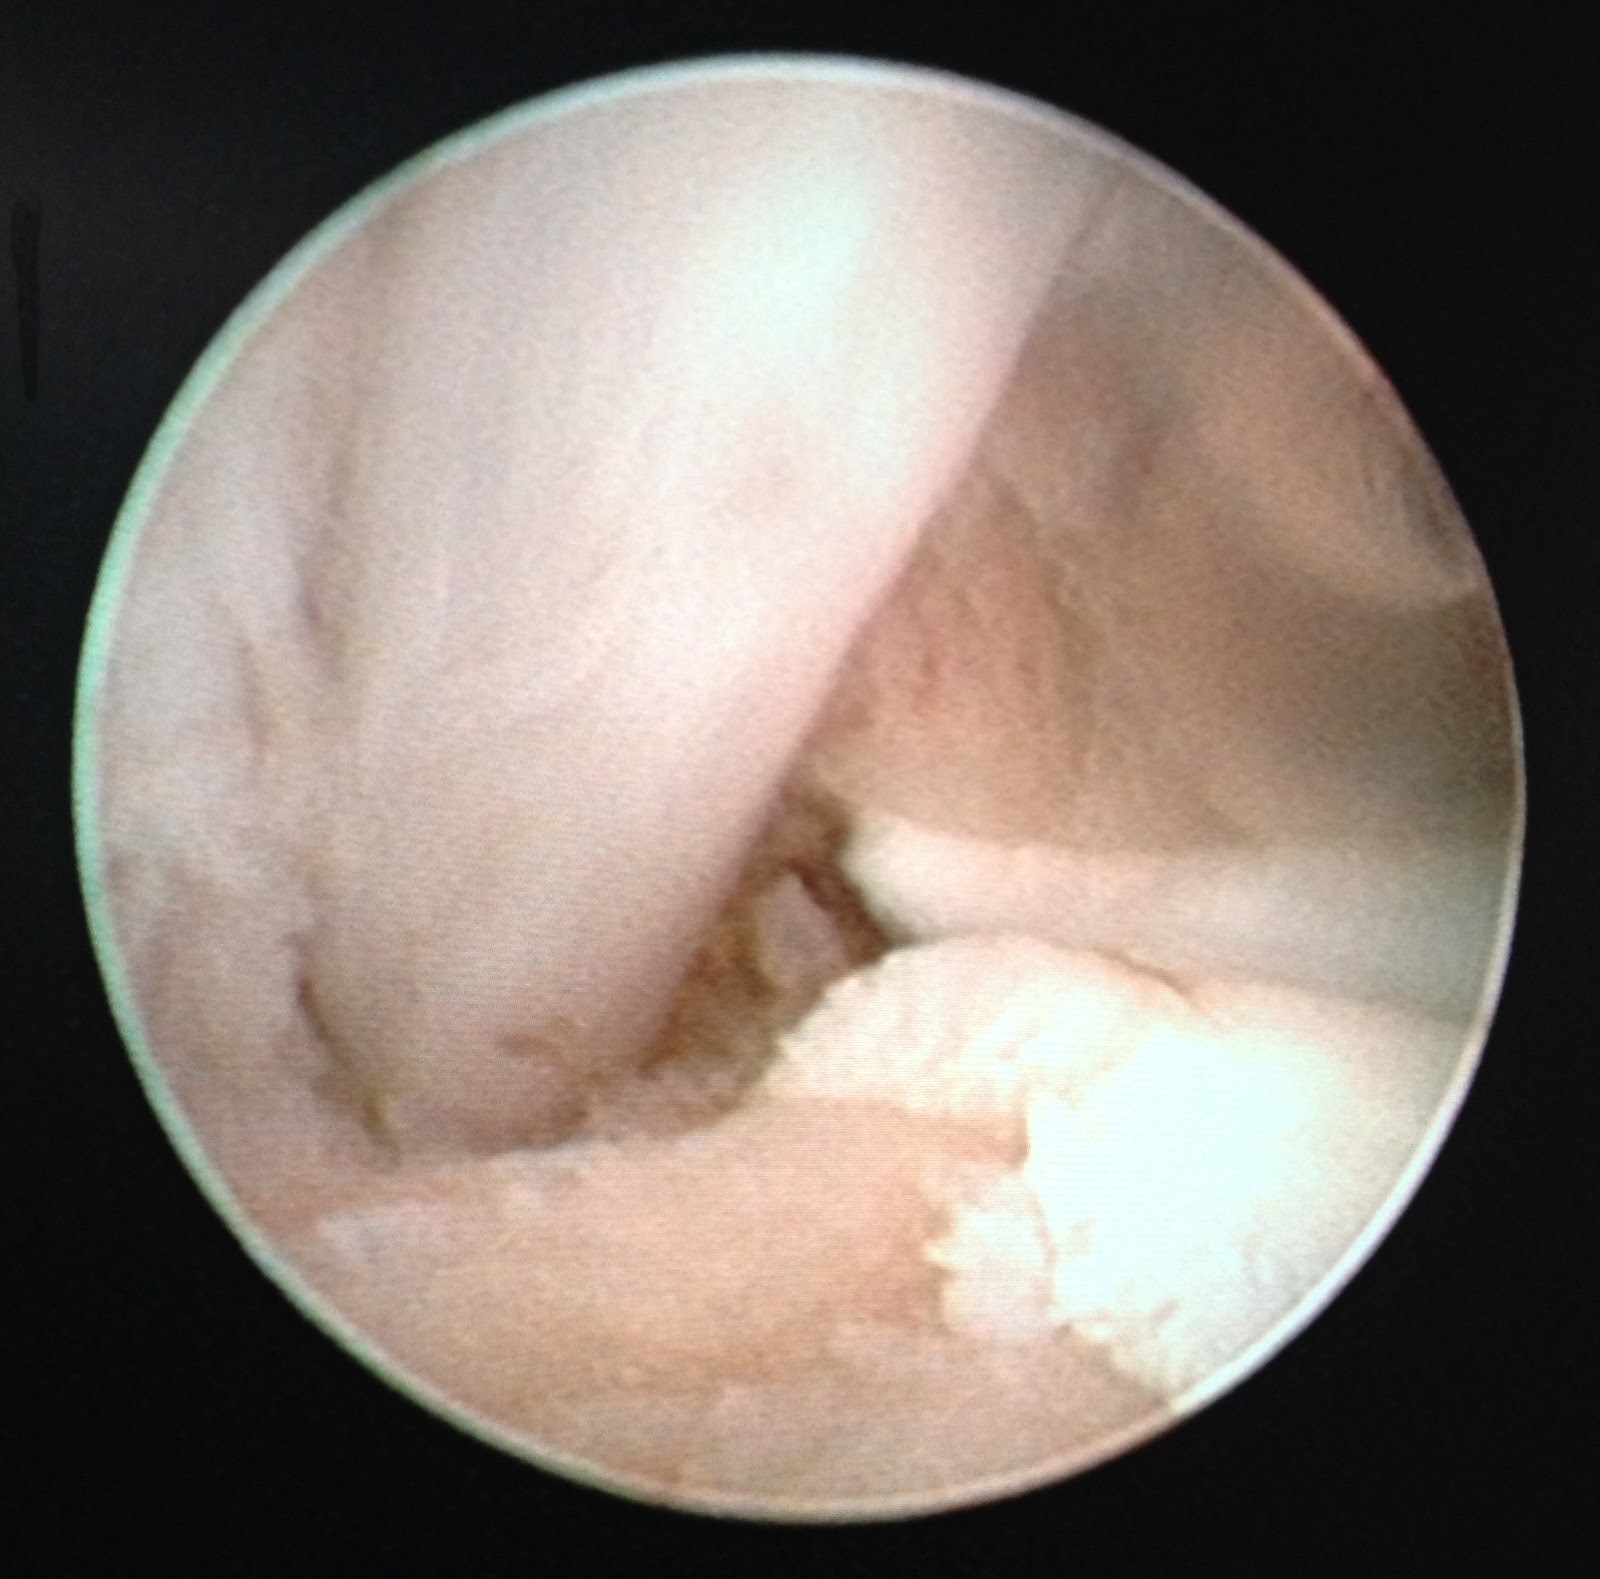

El resto de la ponencia la dediqué a presentar la técnica artroscópica para solucionar este síndrome y los resultados de nuestra ya larga serie de bailarines operados con éxito.

Imagen del FHL pasando junto al proceso posteromedial del astrágaloImagen del FHL liberado tras el gesto quirúrgico sobre el astrágalo